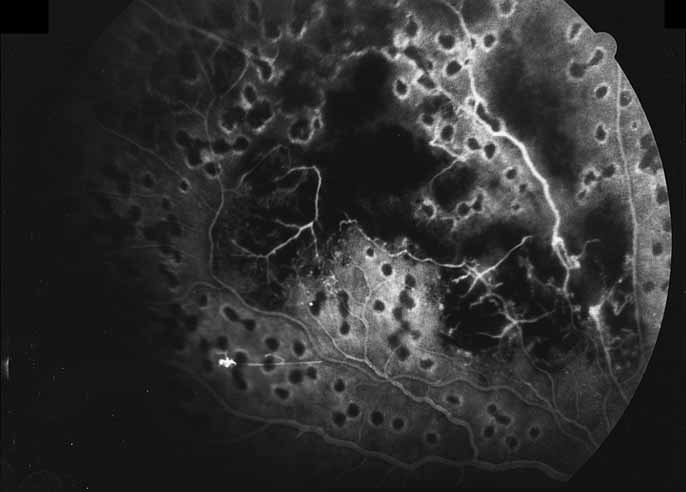

A third instance in which fluorescein angiography concentrating on the optic nerve may be helpful is in eyes with vascular engorgement of the optic nerve, especially with media opacities. Fluorescein angiography may help the clinician distinguish abnormally leaking capillaries from neovascularization. In acute multifocal hemorrhagic retinal vasculitis, optic nerve involvement is common in the early stages of the disease, 47 with optic nerve disc neovascularization seen later (see Figs. 10, 11, 12, and 13). Another fluorescein angiographic clue to the distinction between optic disc vessel engorgement and true neovascularization is the presence of associated large zones of retinal capillary nonperfusion such as those seen in sarcoidosis (see Figs. 14 and 15),34–40 acute multifocal hemorrhagic retinal vasculitis (see Figs. 10 and 11),47 or Eale disease (see Figs. 16 and 17).48–52

Fig. 11 Acute multifocal hemorrhagic retinal vasculitis. Fluorescein angiogram confirms the presence of associated retinal capillary non-perfusion without neovascularization at the onset of the disease.

Fig. 12 Acute multifocal hemorrhagic retinal vasculitis. The patient later developed disk neovascularization with vitreous hemorrhage. Note the areas of neovascular leakage from the optic nerve.

Fig. 13 Acute multifocal hemorrhagic retinal vasculitis. The patient underwent scatter laser photocoagulation to the zones of retinal capillary nonperfusion, which resulted in regression of the neovascularization.